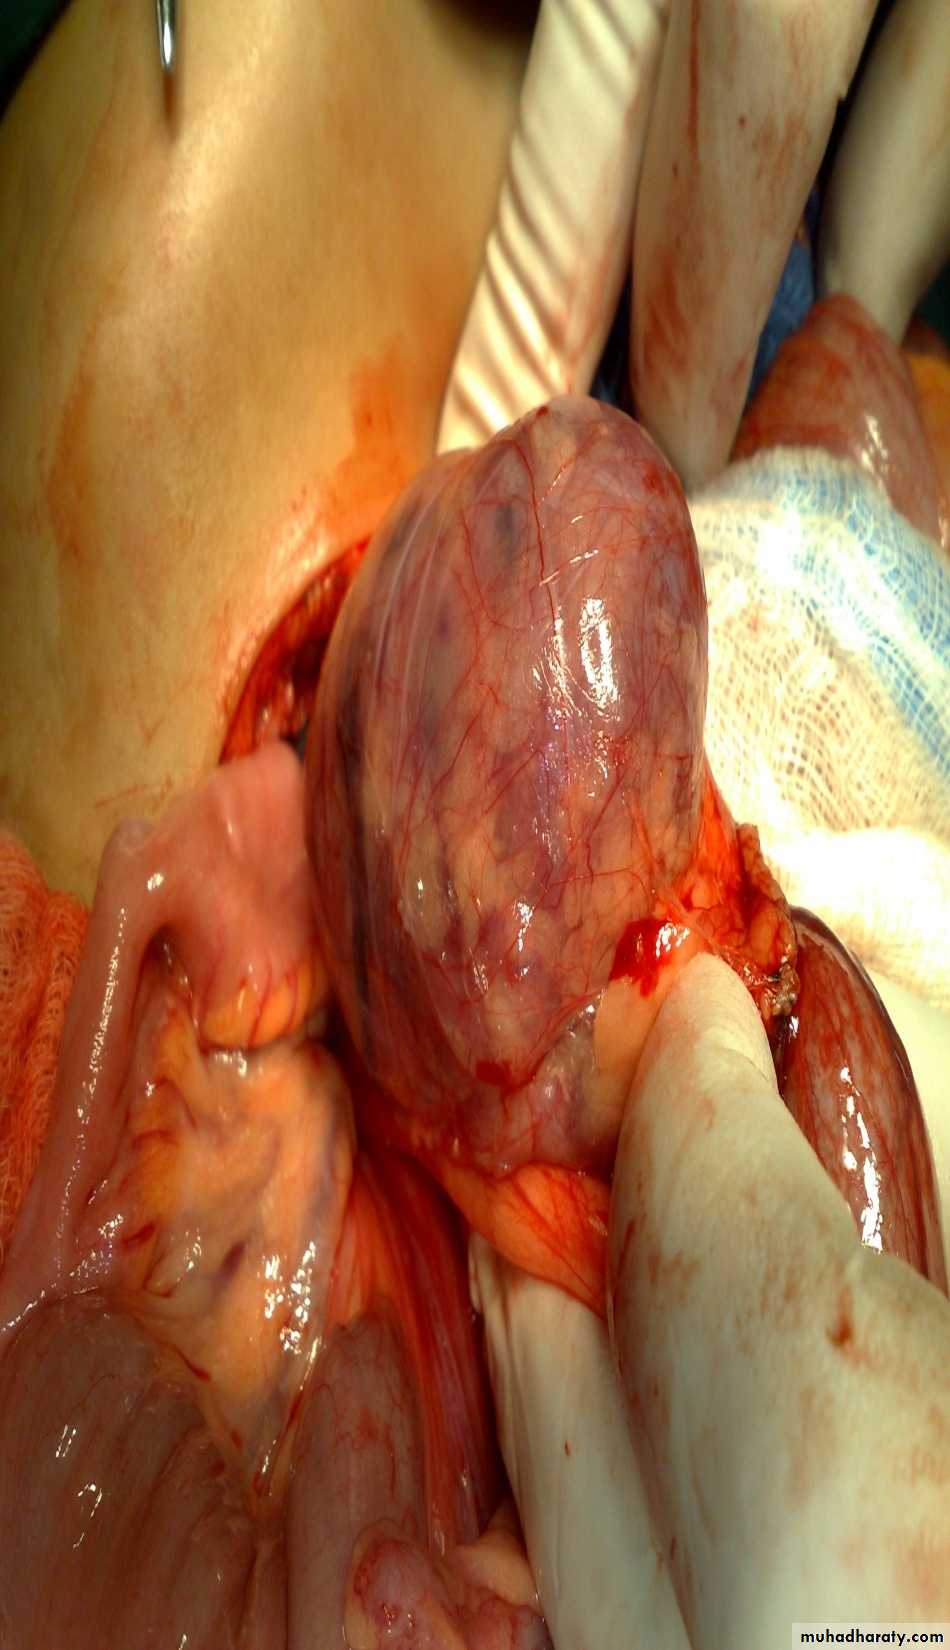

First photo:

Diagnosis: rectal prolapseCauses:

• Constipation or diarrhea

• Weak pelvic muscles

• Worm (trichuris trichiura)

Grades:

• Grade1 يطلع ويرجع conservative treatment by taping

• Grade2 يطلع ويحتاج الى دفع للدخول surgery (Therach operation)

• Grade3 يطلع وما يرجع ابد surgery (Therach operation)